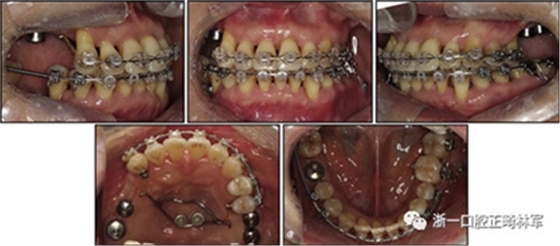

由于患者有多個缺失的后牙,因此考慮到具有垂直方向的喪失。然而,她在拔除后牙后立即去正畸科就診。她封閉了天然的左側前磨牙,并且沒有前牙的咬合磨損。因此,垂直維度被維持是確定的。在正畸治療過程中,牙種植體植入在上頜后牙區(qū)和下頜右側第一磨牙的位置(圖9)。

經(jīng)過3個月的骨結合后,種植體用臨時冠修復以支持垂直維度。

圖9. 上頜牙齒推向遠中,糾正下頜左側磨牙的傾斜度,并放入種植體

在患者適應了垂直維度和咬合后,裝置被去除(圖10)。主動治療時間為17個月。牙列立即用固定的保持器進行保持,保持器從下頜一側前磨牙到另一側前磨牙,以及從上頜一側前磨牙到另一側前磨牙的臨時牙冠上。此外,真空成型的保持器應用于上下兩個牙弓。